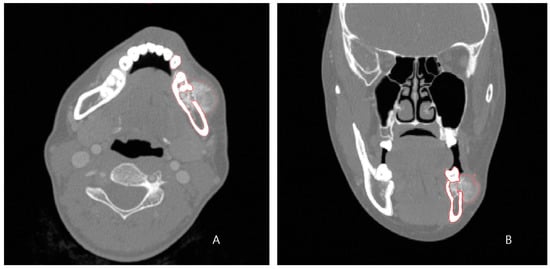

The preoperative patient’s craniomaxillofacial skeleton and lower extremities region-enhanced CT images with slice thicknesses of 1.0 mm were stored in the digital imaging and communication in medical (DICOM) format. These datasets were imported into medical simulation software (Mimics, Materialize NV, Leuven, Belgium) to generate the skull and fibula models through segmentation processing. The standard tessellation language (STL) files of these 3D objects were transferred to medical CAD software (3-matic®, Materialize NV, Leuven, Belgium). The mass was extracted by overlapping the enhanced MRI data with the CT data (Figure 2A), and, based on this, the resection part, including the first premolar to the mandibular notch, was determined with a proper safety margin.

After performing the planned mandibulectomy on the software, mandible cutting guides were designed to implement it (Figure 2B). The left fibula model was moved to the resection area, and the fibula model was positioned at the alveolar level to facilitate later implant placement, considering the fibula’s shape and pedicle location. To achieve this, the fibula cutting guide and the fibula positioning guide were created (Figure 2C,D). In the inferior part, the scaffold that reproduced the original shape of the patient’s mandibular border was designed to partially cover the outer and lower side of the fibular segment to recreate the volume, and, at the same time, it was intended to support the position of the fibula more accurately (Figure 3). Wing-shaped connection parts with fixation holes that could be fixed to the remaining mandible were added on both sides of the scaffold (Figure 2E). All surgical guides and the scaffold were designed to be fixed with screws through fixation holes, and the locations of these fixation holes were shared to enable reconstruction (Figure 2F).

Figure 2. Preoperative 3D simulation for designing surgical guides and patient-specific PCL implant: (A) Mandible model generated from the patient’s CT data and tumor (red) isolated from MRI data; (B) Resection margin (dark gray) with sufficient safety margin and mandible cutting guides (pink) to reproduce it; (C) Left fibula model was moved to the most ideal position at the alveolar level, and the fibula cutting guide (yellow) was designed. (D) Fibula positioning guide (sky blue); (E) PCL scaffold design (blue) to recreate the mandible border below the fibula segment; (F) Fixation holes of all surgical guides are planned to share position vectors (green).